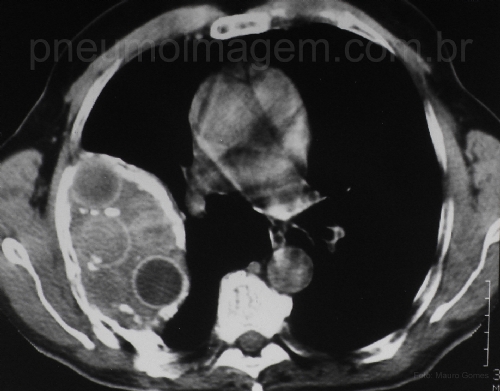

CASO CLÍNICO #4Paciente do sexo masculino, 69 anos, assintomático, encaminhado devido ao achado tomográfico. Nega tabagismo. Refere tratamento para tuberculose 50 anos atrás. Ao exame apresenta deformidade torácica, escoliose, com ausculta pulmonar com MV reduzido em terço superior do hemitórax direito.

Male patient, 69 years old, asymptomatic, referred due to tomographic finding. Denies smoking. Refers treatment for tuberculosis 50 years ago. On examination shows thoracic deformity, scoliosis, pulmonary auscultation breath sounds reduced in the upper third of the right hemithorax.